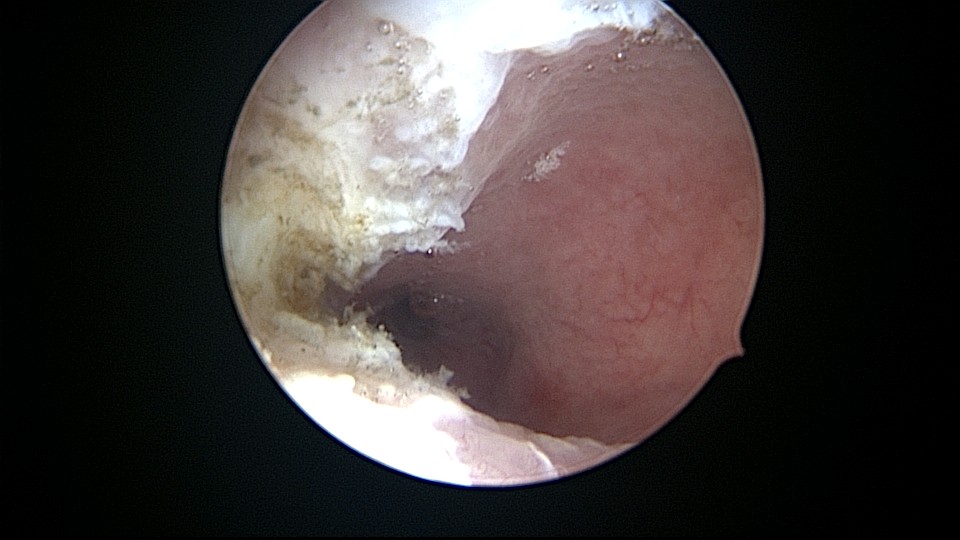

患者32岁,G2P0,自然流产2次,外院行清宫术,术后月经量减少一半。2019年6月市妇幼分粘,术后月经无改善,宫腔粘连复发,2020年11月宫腔镜探查,宫腔中上段幕状粘连,形成两个假的输卵管开口,双极电针分粘,恢复宫腔形态,显露正常的输卵管开口。2020年12月宫腔镜二探取球囊,宫腔形态正常,双侧输卵管开口可见,内膜充血。2022年5月自然妊娠,2023年1月剖宫产分娩一女婴(37+2)。现37岁,G3P1。